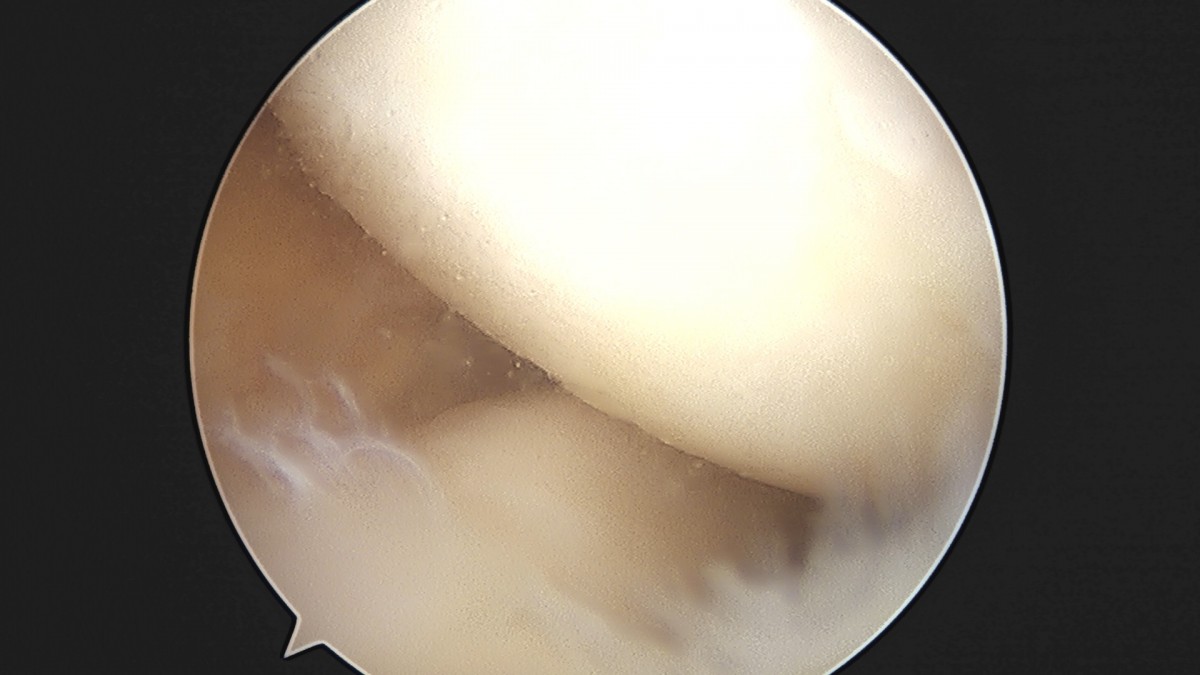

이재상원장님 무릎 반월상 연골판 절제술 조미O 환자

dae765e4d9ac96aee867c9d6292d8784_1758005943_0678.jpg